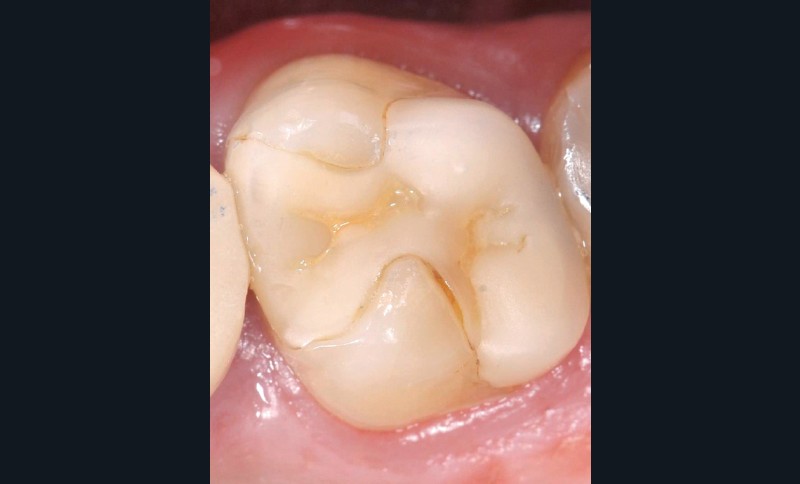

Traitement ultra-conservateur des taches de l’émail : bilan avec 5 ans de recul

Les auteurs de cette conférence nous proposent un algorithme pour résoudre le problème des taches blanches de l’émail. Ces techniques sont désormais utilisées avec succès depuis 10 ans. Tout d’abord il convient souvent de réaliser un éclaircissement préalable : celui-ci diminue le contraste entre la tache et le reste de la dent. Ensuite, avant de poser le champ opératoire, il faut choisir la teinte du composite qui sera nécessaire à la fin du traitement. Un sablage/fraisage des taches les plus profondes est alors réalisé, en fonction de la profondeur de la tache. Vient alors l’infiltration ou masquage optique, qui fonctionne sur les taches blanches : on passe une solution d’acide chlorhydrique, puis une solution d’hypochlorite de sodium, et si la tache est devenue blanche alors il est possible de passer à l’infiltration par la résine. Enfin, s’il subsiste une concavité visible, un composite viendra la combler. Le polissage clôt alors le protocole(fig. 11 et 12).